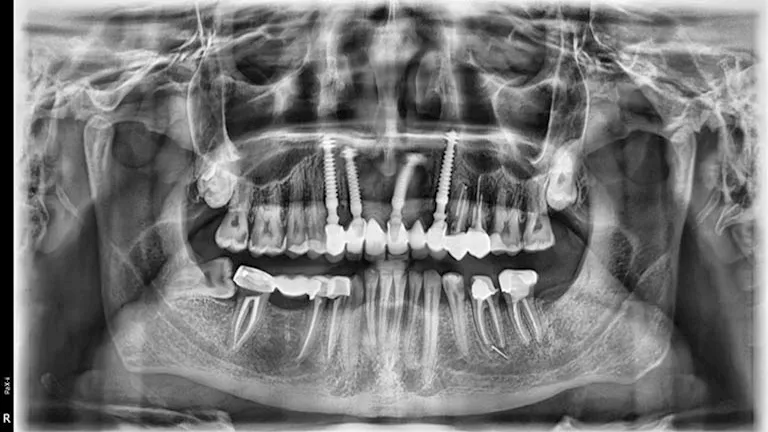

مصراوي - ضحية إهمال طبيب أسنان في الزقازيق يستغيث بوزارة الصحة